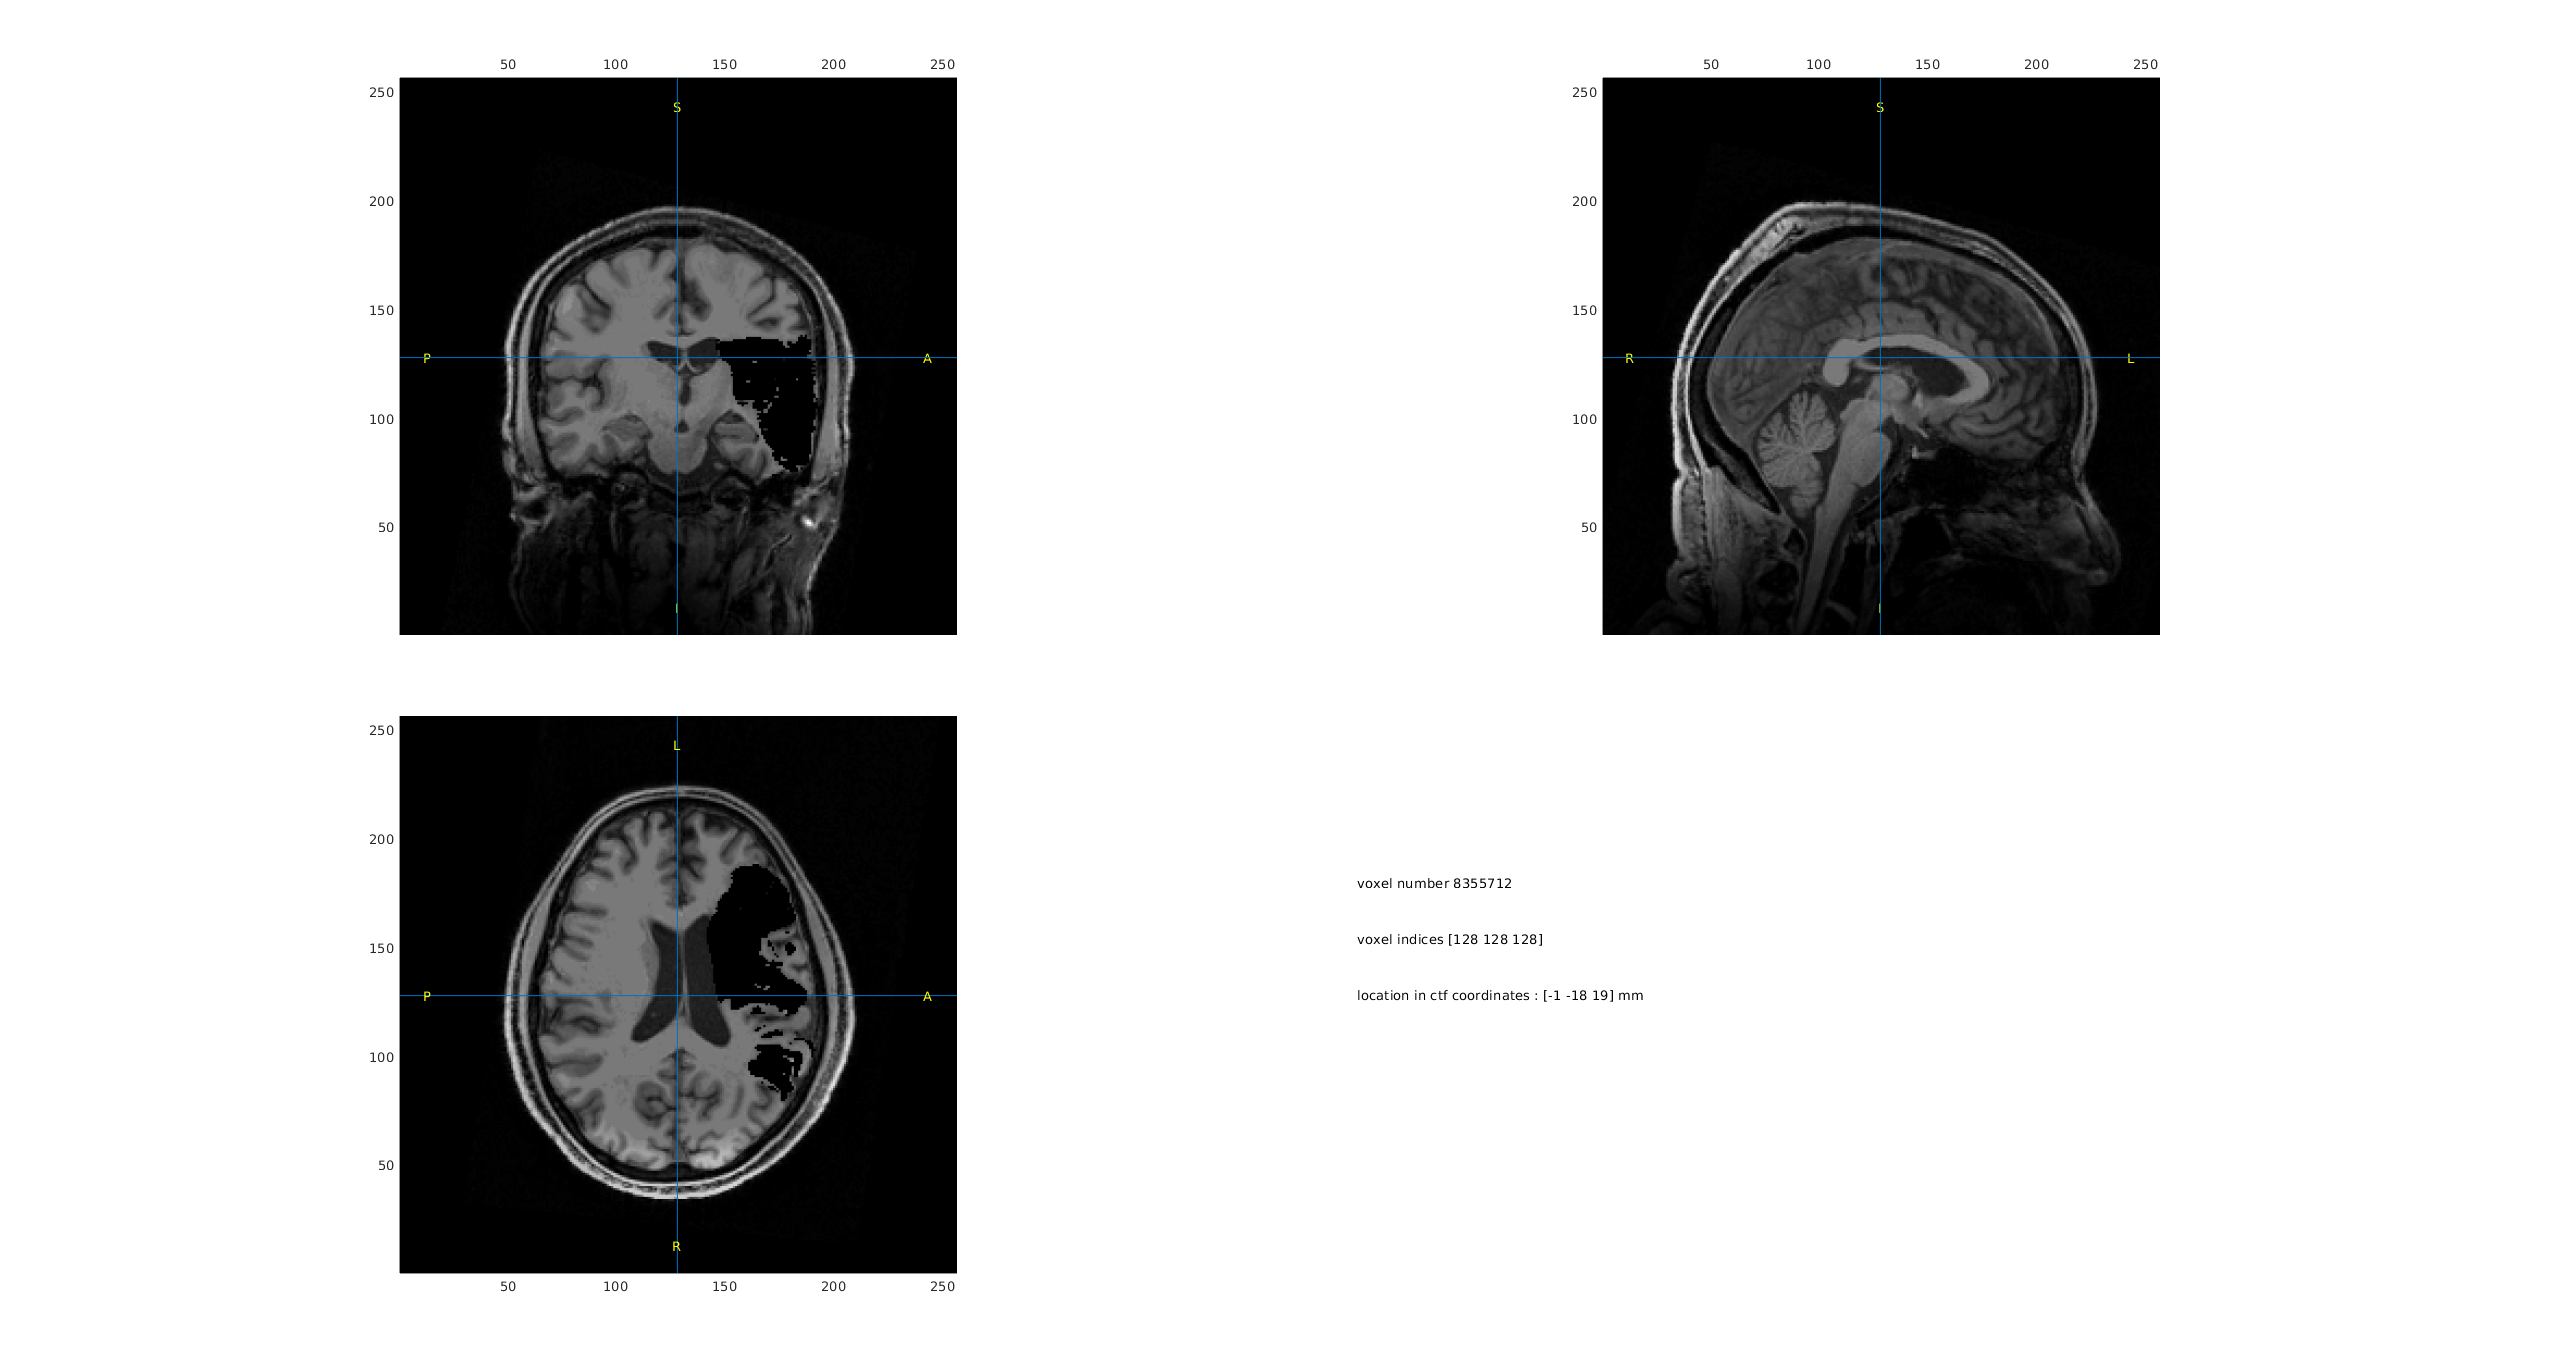

Regarding the segmentation: we actually already have an MRI image where the lesion area has been masked with zero intensity values. When running an indexed segmentation (`ft_volumesegment`) on this image, we observed that the lesion is most often misclassified as scalp or skull tissue (ref. to the joint images).

A non-text attachment was scrubbed...

Name: mri_strok_segmented.png

Type: image/png

Size: 390228 bytes

Desc: not available

URL: <http://mailman.science.ru.nl/pipermail/fieldtrip/attachments/20250619/2ccb1b40/attachment-0002.png>